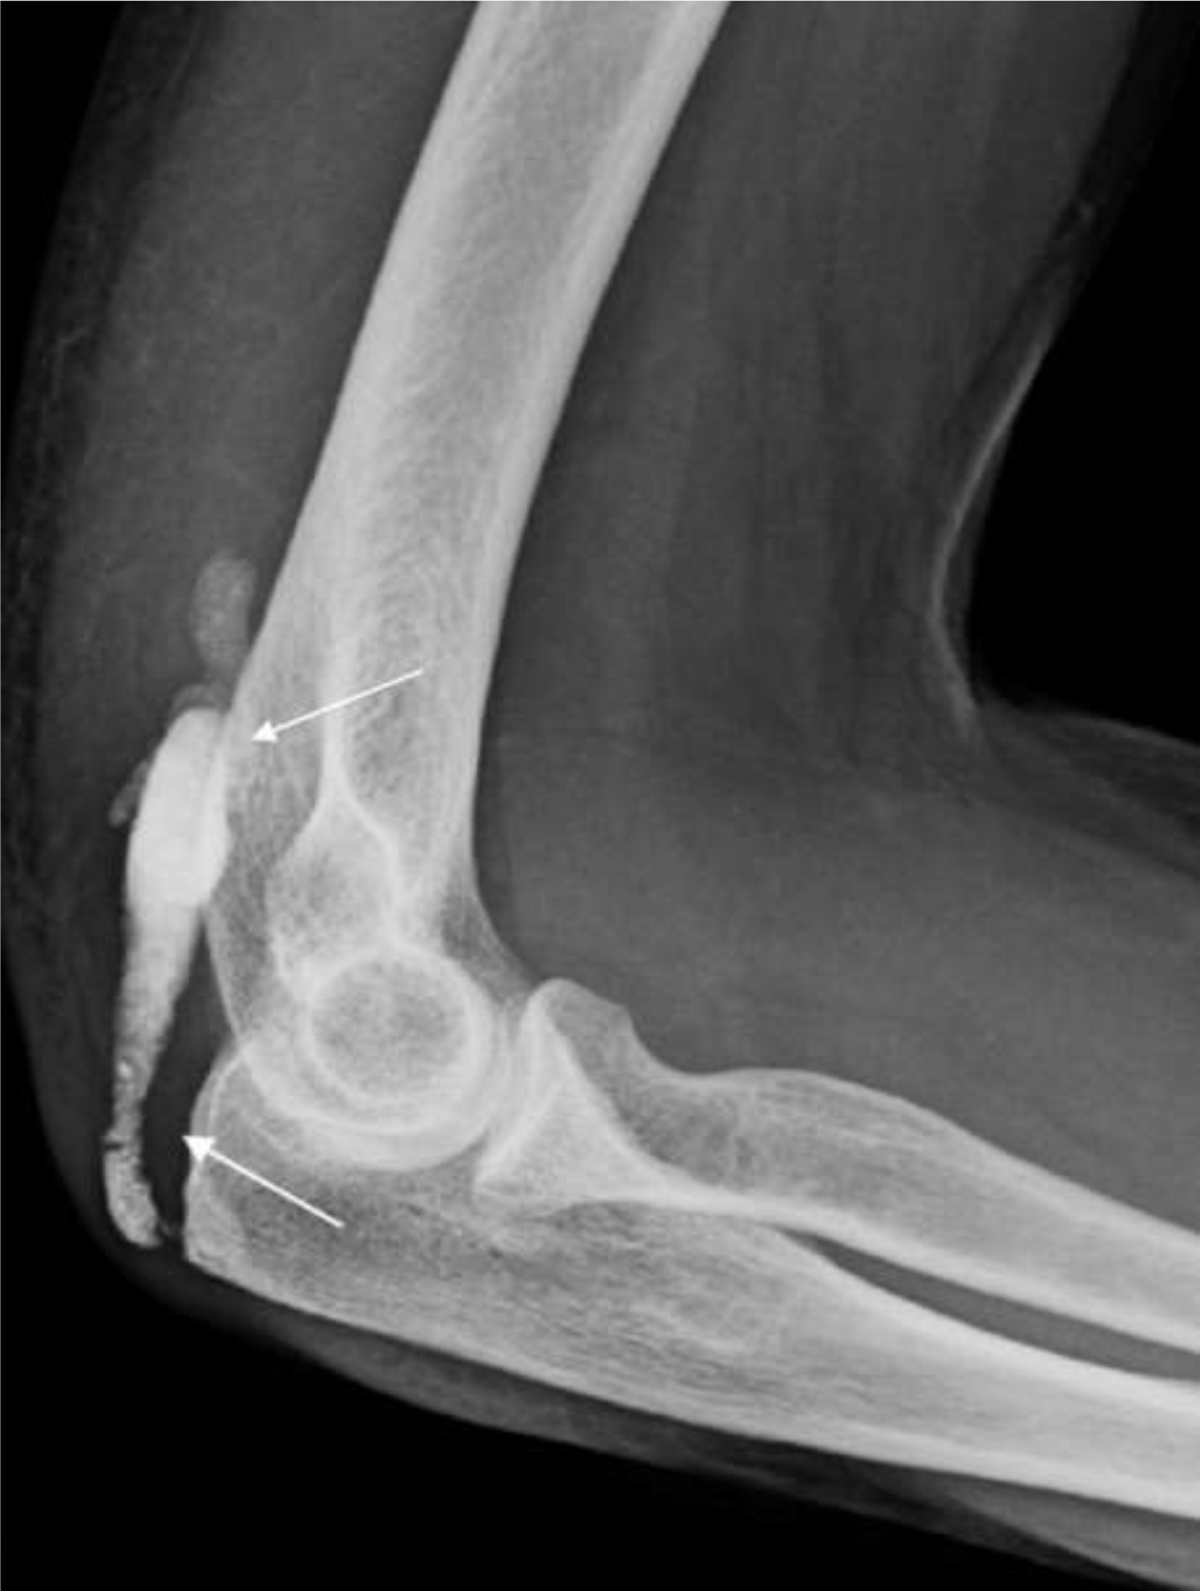

A subsequent conventional radiograph confirmed a well-defined soft tissue calcification with variable density posteriorly to the distal humerus (Figure 2, white arrows). Computed tomography (CT) was performed to further evaluate its extent, morphology, and internal structure. CT confirmed an elongated lesion with “string of beads” morphology within the triceps muscle and tendon. The proximal part was less dense (Figure 3, void white arrows) than the homogeneously hyperdense distal part (Figure 3, white arrows). The olecranon erosion had a subtle central calcification and a sclerotic rim (Figure 3, white circle).

Figure 2